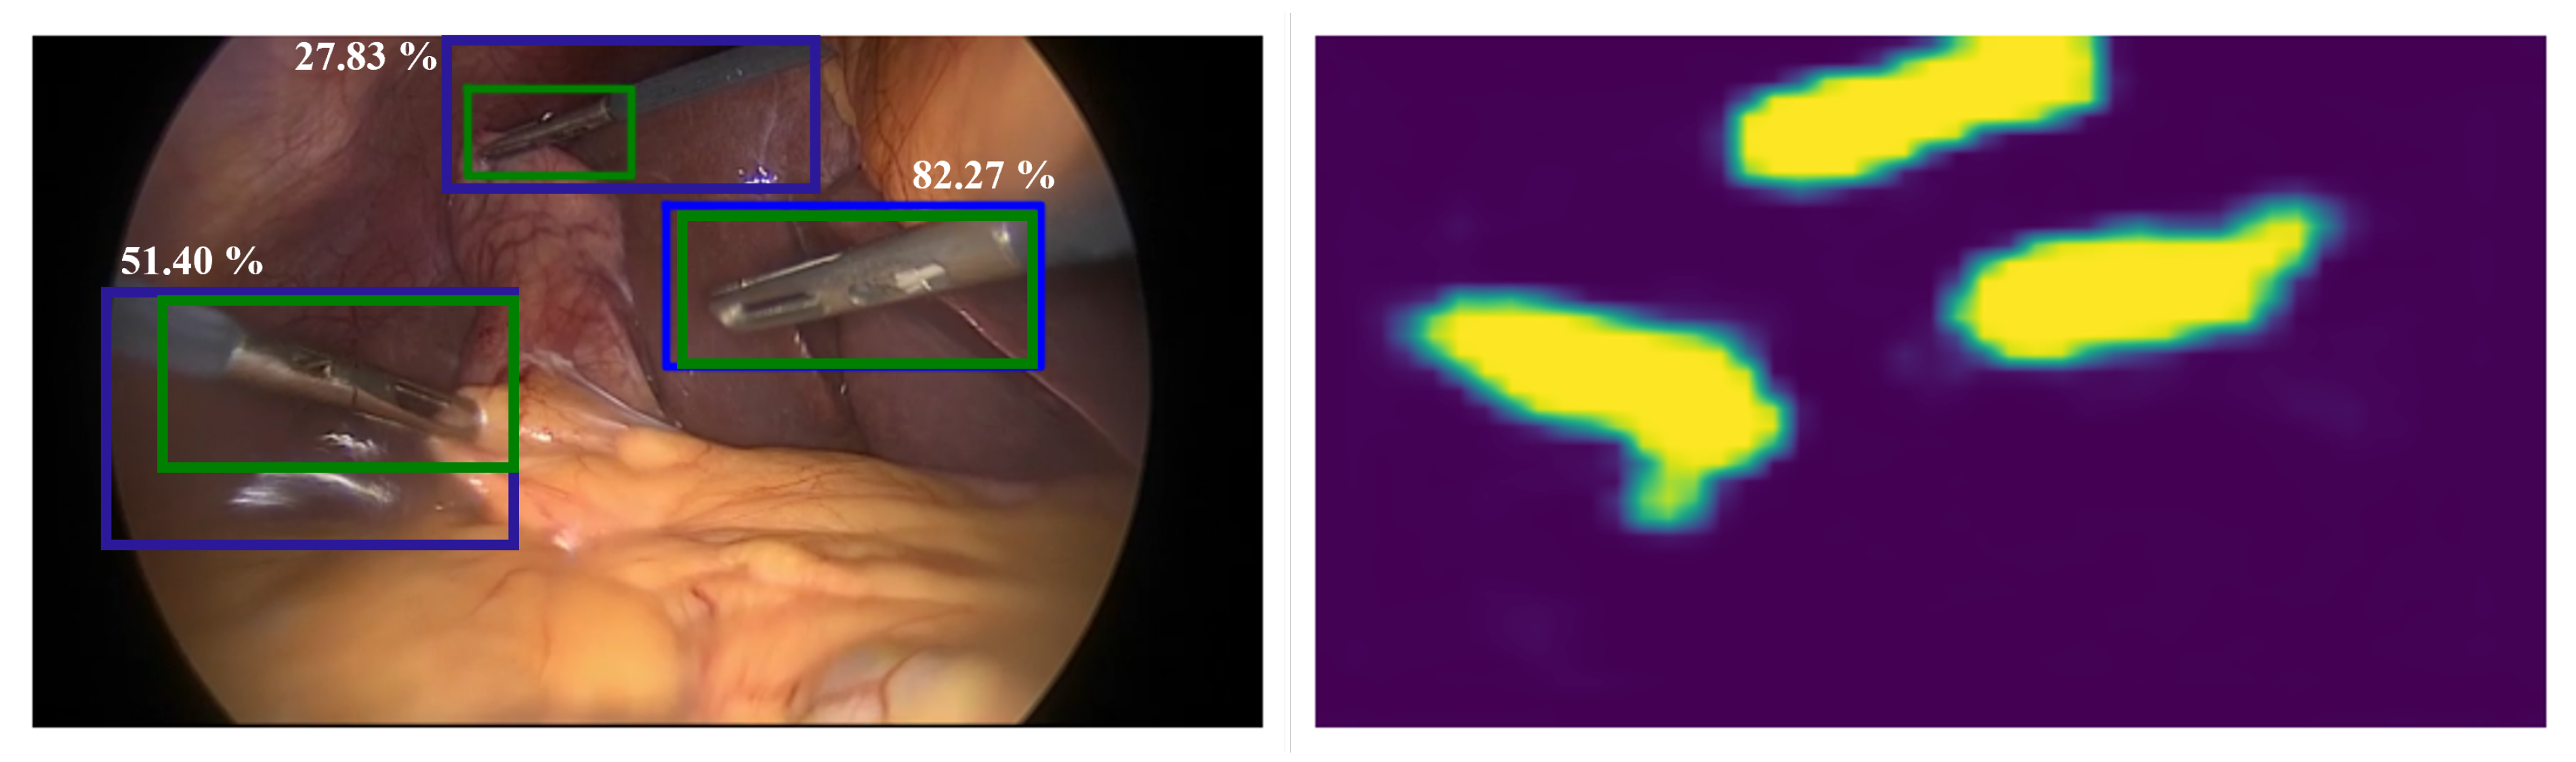

In order to provide insight into the performance improvement achieved by the proposed approach, qualitative results for tool detection and phase recognition were visualized. Figure 5 visualizes localization maps of every tool obtained by the CNN-MMC and CNN-SE-MSF models. Every image contains the manually labeled bounding box and the predicted bounding box of the corresponding tool, and is labeled with the IoU value between the two boxes. The examined tool class probability was higher than 98% obtained by CNN-MMC or CNN-SE-MSF for all images. Figure 6 shows the predictions and ground truth of the top-3 and bottom-3 procedures for surgical phase recognition.

Figure 5.

Visualization of localization maps of the CNN_MMC and CNN_SE_MF approaches for the seven surgical tools. For each tool, the manually labeled and predicted bounding boxes are visualized in green and blue, respectively. Images are labeled with the IoU (%) between the predicted and manually labeled boxes.

In the Cholec80 dataset, the grasper has multiple tool instances (i.e., up to three graspers may appear in the image) while all other surgical tools have a single tool instance. The proposed approach was designed to generate one localization map per tool, Nevertheless, multiple instances of the grasper were detected through a post-processing step. Here, the largest three objects in the localization map of the grasper were considered as ’detections’, and the bounding boxes were assigned the same confidence that represents the grasper presence probability. Figure 7 shows an example of multiple instances of the grasper and the detected bounding boxes. As can be seen, the proposed approach was able to localize the three instances of the grasper, however, only two of the ’detections’ were considered as with IoU greater than . The region that contained the shaft of the third grasper (with IoU = 27.83%) was also detected in the localization map as part of the tool and not only the characteristic tip. Indeed, the weakly-supervised training of the proposed approach resulted in relatively larger bounding boxes that included the tip and parts of the tool shaft. In principle, the shaft is also part of the tool but according to the evaluation criteria of this work, only the tooltip should be localized. However, labeling the tool shaft with additional bounding boxes has the potential to better evaluate the performance of the model in terms of the ability to separate background information from tool regions, and potentially also capture the tool orientation as well as location.